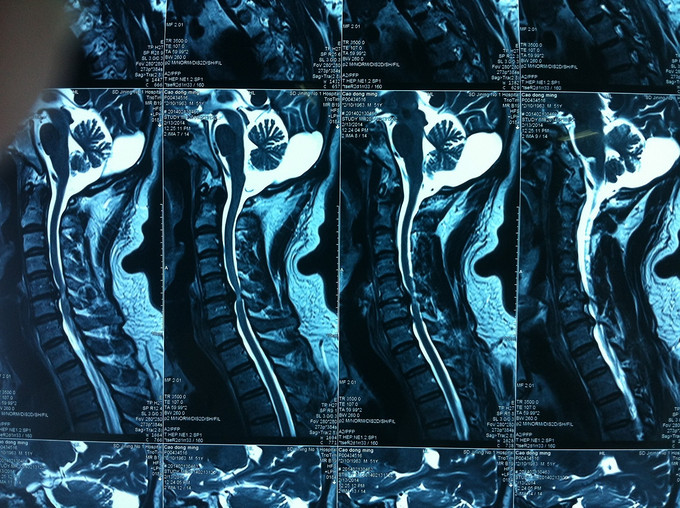

查体:颈后部压痛,颈部活动受限,双侧前臂及手感觉减退,双侧伸腕、伸肘肌肌力4级,双侧霍夫曼综合征阴性,双下肢感觉无减退,双下肢肌张力高,巴氏征可疑阳性,辅助检查: X-ray:劲椎退行性变 CT:颈椎间盘突出,腰5/6 MR:颈椎间盘突出,颈5/6节段明显

诊断:混合型颈椎病 处理: 1、完善相关辅助检查,明确诊断,有无手术指证; 2、完善手术评估,有无手术禁忌,手术风险及并发症; 3、在全麻下行颈椎前路减压,颈5/6椎间Cage植骨融合内固定术

随访 1、术后患者颈部疼痛较前减轻,双侧上肢疼痛、麻木感觉较前好转,双侧伸肘、伸腕肌肌力4+级。 3、术后1个月,患者上肢麻木明显好转,左侧伸腕、伸肘肌肌力4-5级。 讨论:1、颈椎病手术指证的把握,牵引药物保守治疗与手术减压的选择? 2、颈椎手术前路与后路的手术选择?是否考虑以下问题:1、神经根型与脊髓型;2、是否合并椎管狭窄;3、是单双节段还是多节段间盘突出;4、颈椎前路单间隙还是椎体次全切